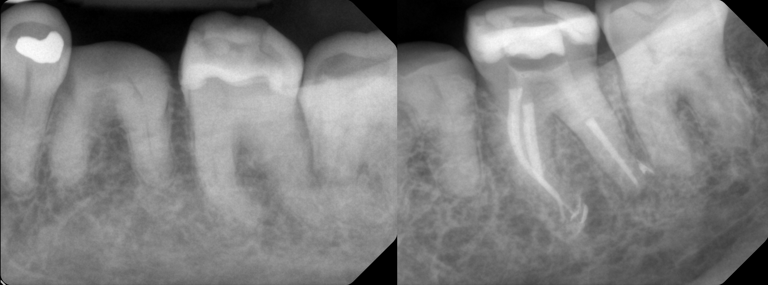

Gallery 1: Initial Cases

Initial Root Canal Cases with preoperative and postoperative radiographs.

#2 RCT with 4 canals

#19 RCT with 4 canals

#3 RCT with 4 canals

#14 RCT with extreme calcification & 4 canals